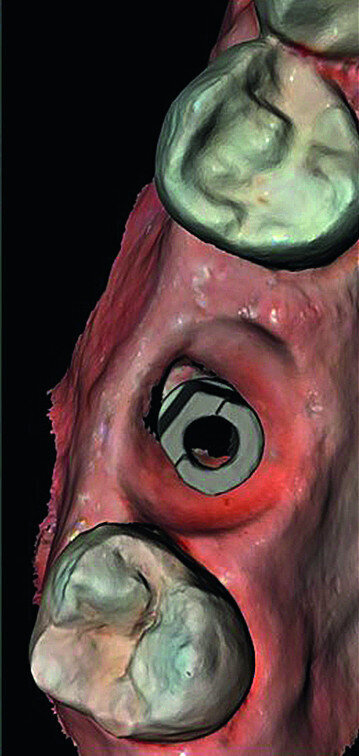

Once the implant bed had been prepared, a 7 × 10 mm implant (AnyRidge) was placed. After placement, the ISQ (Implant Stability Quotient) was measured with a stability meter (Mega ISQ, MegaGen), and the value was 72. According to the ISQ scale, this represents high stability (Fig. 6b). A 10 × 7 mm healing screw (AnyRidge) was placed, along with a plug of A-PRF (advanced platelet-rich fibrin; PRF process by Choukroun) in order to accelerate the healing process, and sutured with 4/0 polypropylene (Hu-Friedy; Figs. 7–10). After the surgical procedure, the White Clinic postoperative protocol was applied: application for eight minutes of the ATP38 laser (Swiss Bio Inov), based on the principle of Low Level Laser Therapy that acts on the cellular metabolism and provides a better and faster postoperative healing. The patient was instructed to use a 0.2% hyaluronic acid gel (Gengigel, Ricerfarma) and 0.1% hyaluronic acid mouthwash (Gengigel First-aid, Ricerfarma) for one week after surgery, with the goal of accelerating the healing process. One week after surgery, the sutures were removed, ozone was used to disinfect the area around the implant, and the ATP38 was applied for eight minutes to promote healing.